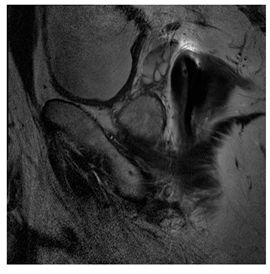

Breast-MRI-NACT-Pilot is an MRI-type image database, collecting breast medical images of 64 patients. Some samples are shown in Figure 12a.

Figure 12.

Sampled images in the tested benchmark databases: (a) Breast-MRI-NACT-Pilot (breast), (b) ACRIN-DSC-MR-Brain (brain), (c) NIH (chest), (d) Lung-PET-CT-Dx (lung), (e) Prostate-MRI (prostate), and (f) Other grayscale standard images.

- (b)

- ACRIN-DSC-MR-Brain database (available at: https://wiki.cancerimagingarchive.net/pages/viewpage.action?pageId=50135264 (accessed on 4 November 2021))

ACRIN-DSC-MR-Brain database contains MRI-type and CT-type brain medical images. Some samples are shown in Figure 12b.

- (c)

- NIH Database

ANIH is an X-ray type image database collecting chest medical images. Some samples are shown in Figure 12c.

- (d)

- Lung-PET-CT-Dx Database (available at: https://wiki.cancerimagingarchive.net/pages/viewpage.action?pageId=70224216 (accessed on 4 November 2021))

Lung-PET-CT-Dx is a CT-type image database collecting lung medical images. Some samples are shown in Figure 12d.

- (e)

- Prostate-MRI Database (available at: https://wiki.cancerimagingarchive.net/display/Public/PROSTATE-MRI (accessed on 4 November 2021))

Prostate-MRI database contains MRI-type medical images and collects prostate medical images. Some samples are shown in Figure 12e.

- (f)

- Other grayscale standard images

In order to investigate the flexibility of our method, we also tested several available images, as shown in Figure 12f.